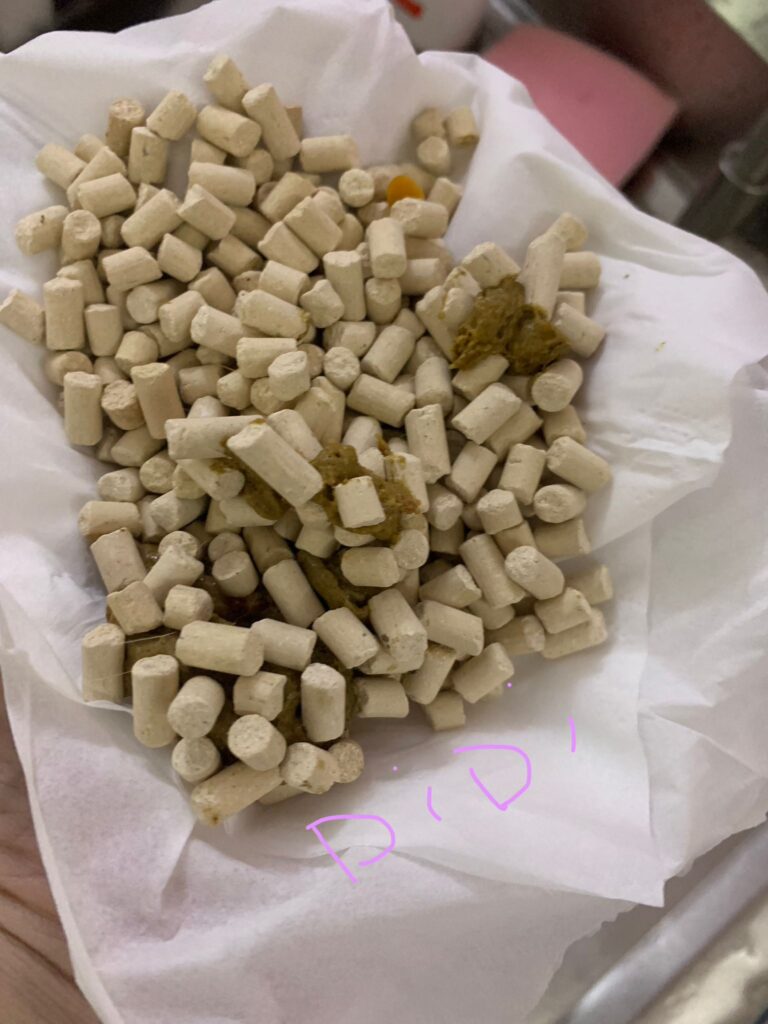

1pm: poo 4.5/10

Morning: didi constipated, saw him in 2 bins, trying to squeeze out something n can’t n he try to rub on floor – aren’t that pushing that piece in? I help him push out the 2cm piece 5/10, and he go to bin 03 and poo out another 12cm. So is that piece stuck n he is so uncomfortable. Subcut him w bupre also. His f patch still on. Can tear off soon. Need to buy more

Morning: sometime he will meow n meow at me. Want me sayang? In pain? Want some snacks? I sayang, f patch still on. I give him kelly n co fish don’t want, some Korean ciao like treat don’t want, given pidan prawn also don’t want. Have to think of what to bring over for him. Poo 4.5/10

Night: poo long n firm 5/10

7am+: he poo 1.5/10 w tinted blood. Reaction to niramine?

Night: poo 5/10, poo when i about to leave. Erm. Nice formed not much smell

He poo 1.5/10, w blood (dr d says may be due to stress)

Poo 2/10 paste, given probiotics

1pm+: poo 2.5/10, give probiotics and nutriplus gel. Given Subcut w b12 bcom.

He poo again 2.25/10.

Morning: poo like ice cream cone texture, small smelly!!